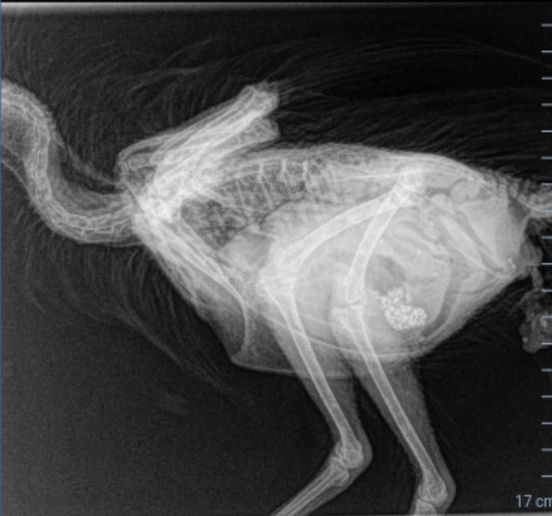

Today she was very off and I took her into my work (a vet hospital) but she died on the way. I took an X-ray but the doctors I work with don’t have experience with chickens. Is there anything abnormal on it? – Kim Marsman

Dr Bowes: What lice treatment was used? Some products, such as Malathion and other organophosphates used at the wrong dosage are toxic. The positioning of the body for the X-ray obscures the abdominal cavity, but I don’t see anything obvious that would explain her death.